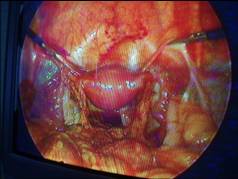

(3)再次手術時發現:剖腹探查可見盆腔緻密粘連,在盆底、骨盆漏斗韌帶及輸尿管上有小結節,或可見到3~10cm大小的盆腔包塊,位於髂內血管附近或陰道殘端側角處與周圍組織如膀胱直腸、乙狀結腸粘連,腫塊還可包繞輸尿管,術中切除之組織送病檢證實為卵巢組織。

3.手術治療 手術切除卵巢的殘餘物仍是主要的治療方法,既可進一步明確診斷,又可做到徹底治療。10%~30%的ORS患者於術中不能完全切除卵巢殘留組織,8%~10%的ORS患者術後仍有復發可能手術時應仔細分離後腹膜,暴露輸尿管及主要血管,以便完全切除殘餘的卵巢組織。由於卵巢殘餘物綜合徵往往發生於困難手術或多次手術後患者盆腔粘連顯著需廣泛分離故手術時間較長,失血量較多,文獻報導平均失血量600ml(200~1000ml)手術併發症亦較多,如輸尿管和腸道的損傷,有的病例因緻密粘連而行腸切除及腸吻合術,有的因輸尿管損傷而行輸尿管膀胱吻合術有的行探查性膀胱切開術。對有泌尿道症狀者術中作膀胱鏡和逆行腎盂造影術,並在探查卵巢殘餘物前置輸尿管導管,以避免損傷輸尿管Unger等(2001)報導1例卵巢殘餘物綜合徵,其卵巢殘餘物累及腹下血管則手術需切除受累的腹下動脈。

至於腹腔鏡在ORS診斷和治療中的套用Howard曾報導關於根據CPP患者病史、非侵襲性試驗的物理診斷和發現的評估,4%以上用腹腔鏡診斷其中約65%的CPP患者至少經腹腔鏡可作出一種診斷:1/3為子宮內膜異位症;1/4為粘連;余為卵巢囊腫、疝、盆腔淤血綜合徵卵巢殘餘物綜合徵等不過腹腔鏡在卵巢殘餘物綜合徵或殘餘卵巢綜合徵中的套用,文獻報導意見尚不一致,有的作者認為其作用有限,有的作者則認為腹腔鏡較其他手術方式價廉、併發症少、住院時間短;Kamprath等認為腹腔鏡尚可經腹膜後進入,在盆腔邊緣分離輸尿管骨盆漏斗韌帶,可有效地切除殘餘卵巢組織。腹腔鏡或剖腹探查的選擇應根據手術困難的程度和手術者的經驗而個體化。